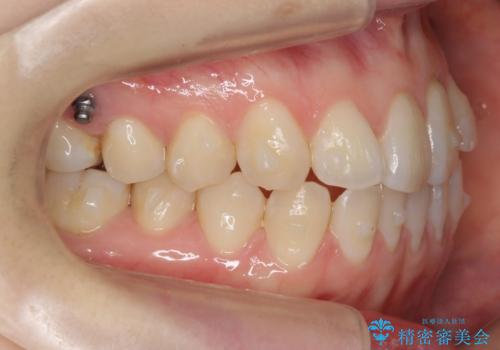

左上の前歯が飛び出しており、唇が笑った時に引っかかっていたのが解消しています。

左上の前歯は小さいため、(矮小歯)左右対称になるようにセラミックで形を修正する治療も併用しています。

歯を大きくかぶせるスペースを作るため、右上の奥歯を後ろに下げています。

矯正用ミニスクリューを1本、使用しています。

左にずれていた上の正中も揃い、大変喜んでいただきました。